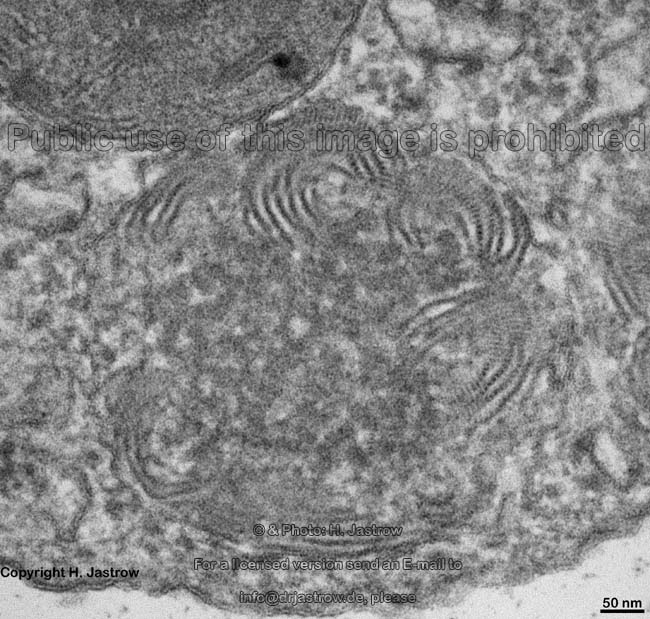

Elektronenmikroskopisch enthalten Mastzellvesikel verschiedene Komponenten: zum einen zylinderförmige, lamellierte an Membranrollen erinnernde Strukturen (im Detailbild 1 in Quer und Längsschnitt erkennbar), ferner kristalline Komponenten (erkennbar an der regelmäßigen Streifung; Detailbilder 1-5). Einige Autoren wollen Ribosomen in Mastzellvesikeln kultivierter Zellen gefunden haben.

Typ 1 die häufigsten, in der Haut vorwiegenden, welche Vesikel mit hauptsächlich amorphem elektronendichtem Inhalt besitzen. Nicht allzu häufig liegen um den dunklen, teils kristalloiden Vesikelkern am Rand rollenförmige Strukturen (Detailbilder 1-5). Diese Mastzellsorte bildet Tryptase und Chymase.

Typ 2 die weniger häufigeren in der Lunge überwiegenden mit besonders vielen Vesikeln mit hauptsächlich rollenförmigem Inhalt sowie osmiophilen Fetttröpfchen unterschiedlich starker Elektronendichte (Detailbilder 6-8). Die Lipidkörper enthalten Cyclooxygenase. Die Mastzellen vom Typ2 produzieren nur Tryptase.